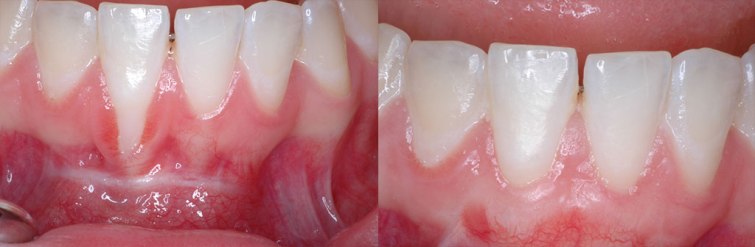

ღრძილის რეცესია, რომელიც ვიზუალურად კბილის ყელის გაშიშვლებით და კბილის გვირგვინის დაგრძელებით გამოიხატება, პაროდონტის დაავადებითაა გამოწვეული. გაშიშვლებული კბილის ყელი, რომელიც სინამდვილეში ფესვის ზედა ნაწილს წარმოადგენს, ხშირ შემთხვევაში ძალიან მგრძნობიარეა და კარიესით ზიანდება, რადგან ფესვის ზედაპირი გაცილებით რბილია, ვიდრე მინანქარი და იგი ძვლითა და ღრძილით უნდა იყოს დაფარული. სწორედ მის დასაფარად და ანატომიური მდგომარეობის აღდგენის მიზნით ტარდება ქირურგიული პროცედურა ღრძილოვანი გრაფტის გამოყენებით.

გრაფტი იგივეა, რაც ტრანსპლანტატი. ღრძილოვანი გრაფტი ღრძილის ქსოვილია, რომელსაც აიღებენ ერთ უბანში (უფრო ხშირად სასაზე) და გადანერგავენ გაშიშვლებული ფესვის ზონაში, სადაც იგი ნაკერებით ფიქსირდება ღრძილოვანი ნაფლეთის ქვეშ. ეს პროცედურა ადგილობრივი ანესთეზიის ქვეშ კეთდება, საკმაოდ ხანმოკლეა, თუმცა ექიმის მხრიდან გამოცდილებას მოითხოვს.